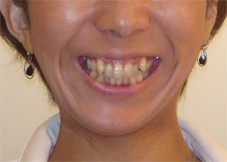

笑った時の八重歯を気にして来院された患者さまです。

写:矯正治療前、右:治療後

上下とも八重歯の状態が治療後は改善しています。歯並びがきれいに並んで、その後ホワイトニングも行いました。

前歯の歯並びのでこぼこも解消しました。

上の前歯が前に突出していた状態も改善して前歯が引っこんでいます。

前歯の歯並びが改善すると笑った時の雰囲気もかなり変わりますよね。この後すぐに結婚式が控えておりましたが、ホワイトニングも行って挙式に臨んでいただきました。